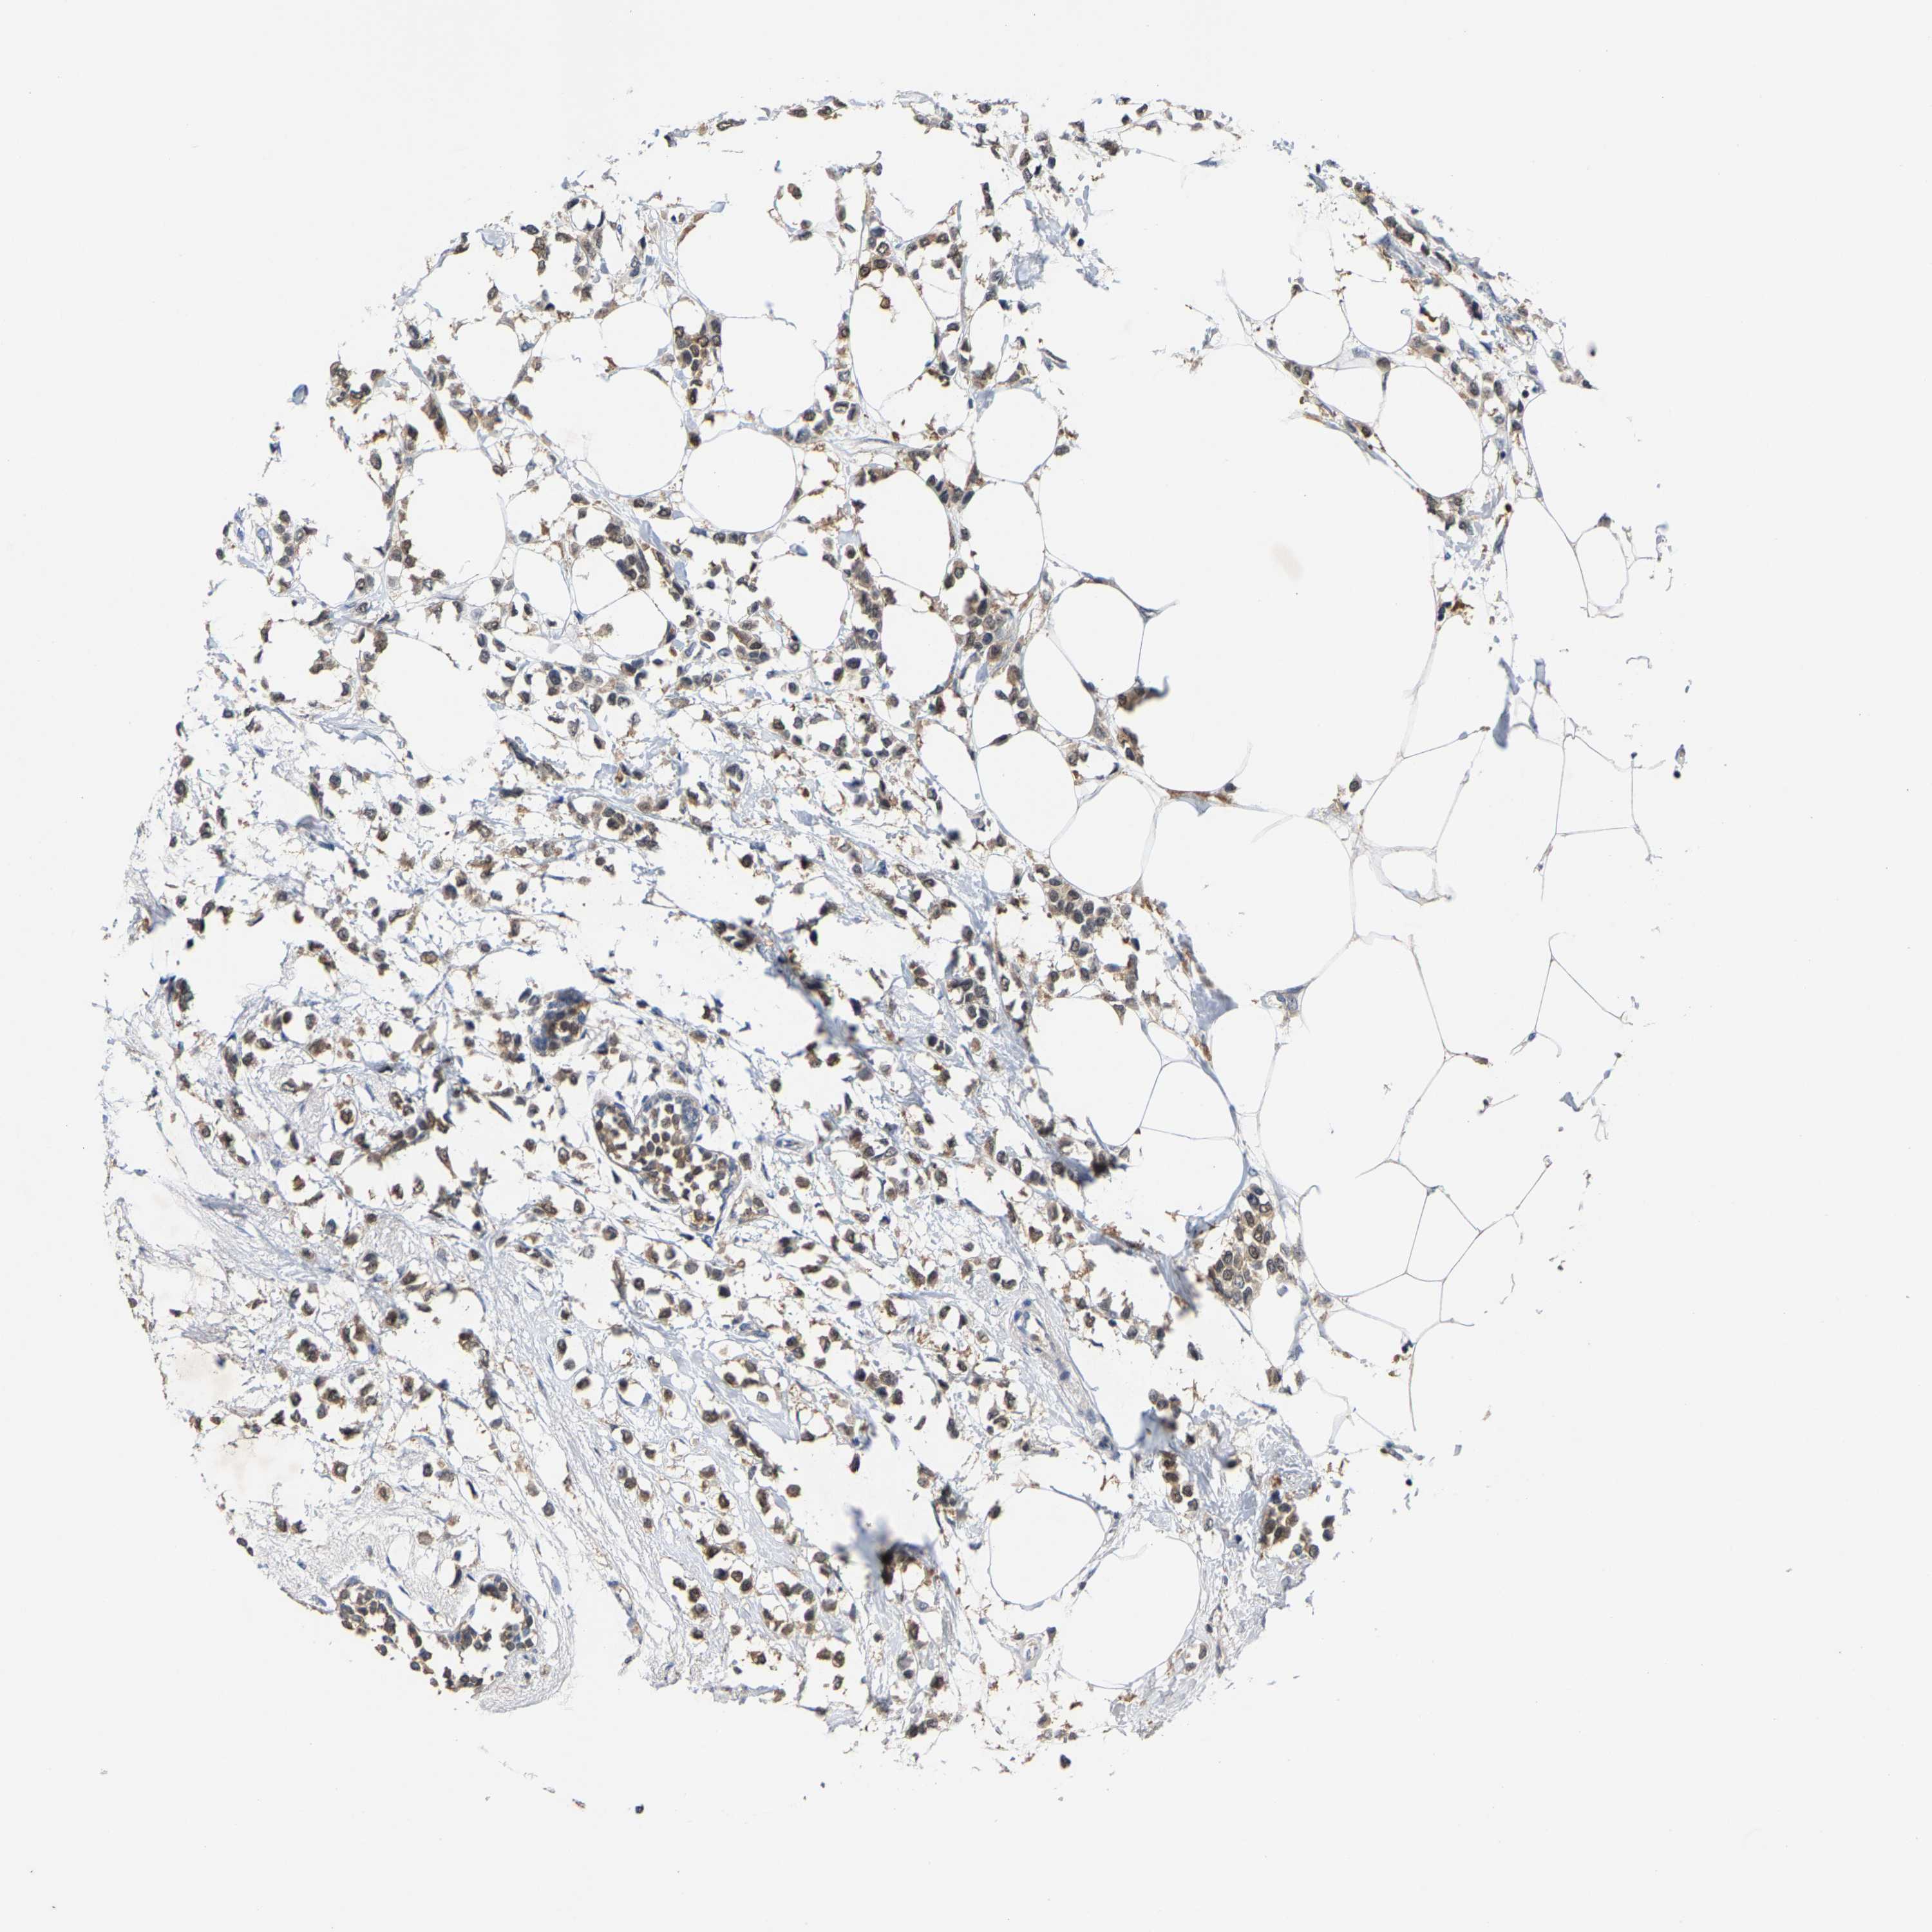

CANCER BREAST CANCER Show tissue menu

BRCA TCGA BRCA VALIDATION PROTEIN EXPRESSION